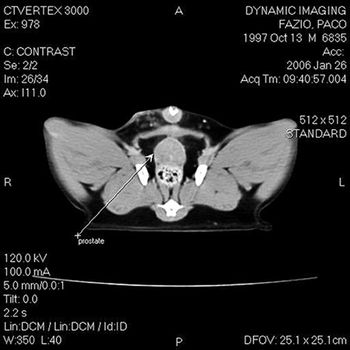

What is your interpretation and diagnosis?

Malignant tumors of the lower urinary tract include transitional cell carcinoma, squamous-cell carcinoma, adenocarcinoma, leiomyosarcoma, fibrosarcoma, hemangiosarcoma and rhabdomyosarcoma.